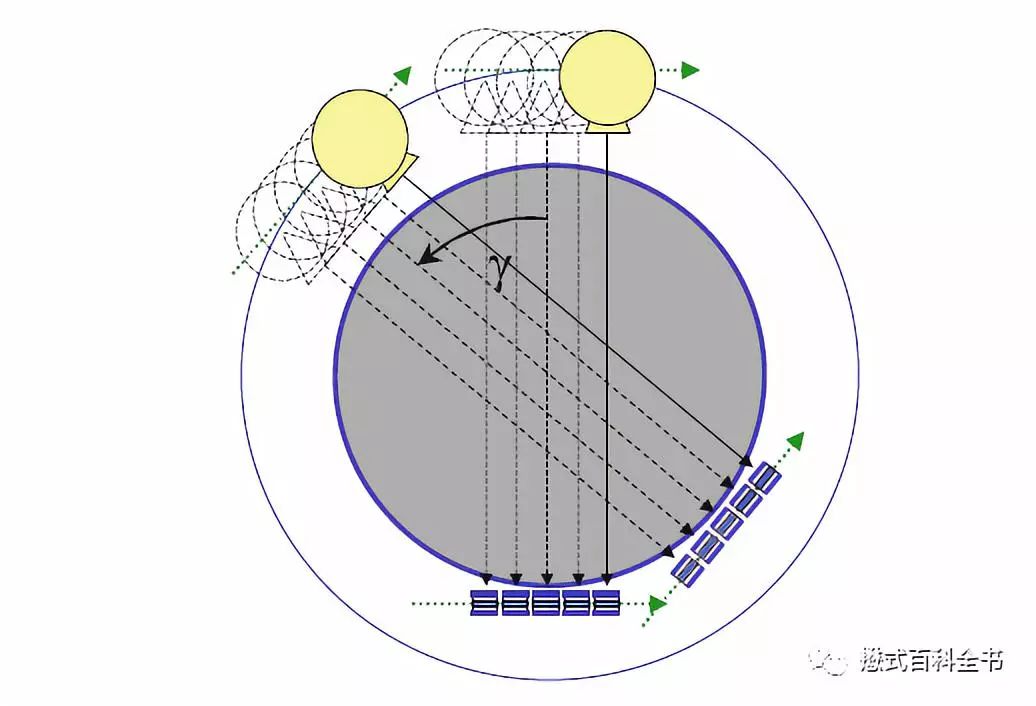

图7:第一代非螺旋CT

第一次飞越是由非螺旋CT发展为螺旋CT,英文Spiral CT或Helical CT,主要的技术革新是利用了滑环技术,探测器可以连续旋转,这次飞越使CT摆脱了逐层扫描的模式。传统的非螺旋CT扫描模式采用的是进步-采集模式,即step-and-shot。这种采集方式包含了两个周期:数据采集周期和非数据采集周期。在数据采集周期,病人不动(扫描床位置不动),X线球管和探测器以一定速度绕病人旋转一周,采集数据;当一层数据采集完成以后,进入非数据采集周期,扫描床移动到下一个扫描位置,等待新的数据采集周期。可以发现,螺旋CT出来之前,CT扫描是采用逐层扫描进床的模式,扫描速度非常慢,而且容易产生伪影,也不方便做一些受呼吸运动影响大的部位。

第二次飞越是由单层螺旋CT发展为多层螺旋CT。多层螺旋CT是指在单层螺旋CT的基础上,增加了探测器在Z轴方向上的-排列数目,这样可以使X线管旋转一周,完成多个层面(断面)的数据采集。相比于单层CT,多层螺旋CT的主要优势在于扫描速度的大幅度提高。扫描速度提高以后,我们可以做很多新的项目,如一些呼吸运动器官的扫描得以实现。另外,由于Z轴(即层面方向)的探测器数目增加,使CT扫描的层厚得以更薄,提高了Z轴方向的空间分辨率或者层间分辨率,这样可以使各项同性成像成为可能。